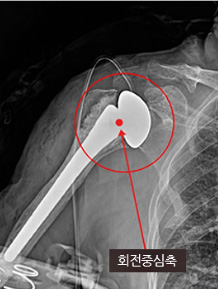

| 구분 | 기존 어깨인공관절수술 | 역방향 어깨인공관절수술 |

|---|---|---|

| 사진 | ![]() |

![]() |

| 대상 |

- 60대 이상 고령층 - 퇴행성관절염, 외상으로 관절기능이 손상된 자 |

- 65대 이상 고령층 - 회전근개 파열로 봉합이 불가능하고 가성마비가 있는 경우. 단, 삼각근은 정상이어야 함 |

| 방법 |

- 65세 이상 고령층 - 본래 골격 모양과 유사한 인공관절 사용 - 뼈를 인공관절로 교체, 힘줄은 봉합 안함 |

- 본래 골격과 반대되는 모양의 인공관절 사용 - 파열된 회전근개 대신 삼각근 이용 |

| 특징 |

- 회전 중심축이 어깨 바깥쪽에 위치 |

- 회전중심축이 어깨 안쪽에 위치 |

| 단점 |

- 통증은 회복되지만 가성마비가 있는 경우 마비 증세는 회복 안됨 |

- 인공관절 각도에 따라 팔 드는 각도 달라져 수술 난이도 높음 |

견관절에 시행하는 인공관절의 일종으로 상완골두와관절와순에 인공관절 기구를 삽입하여 견관절에 작용하는 힘의 방향을 변화시킴으로 남아있는 삼각근이 기능을 할 수 없는 파열된 회전근개를 대신하게 해주는 방법입니다.

기존 인공관절모양과 반대되는 모양의 인공관절을 사용합니다.

원래 둥근 모양의 상완골 끝에 반대로 오목한 소켓 모양의 인공관절 부품을 넣고, 견갑골의 오목한 부위에는 볼록한 공 모양의 인공관절 부품을 사용해 어깨를 올리도록 힘을 받쳐주는 회전중심축 위치를 어깨 안쪽으로 옮깁니다. 이때 상완골을 아래쪽으로 옮겨 팔을 올리는 각도가 좀 더 넓어지도록 합니다.

손상된 회전근개 힘줄기능을 대신해 회전근개 위의 삼각근을 이용, 회전근개 힘줄의 기능을 대신할 수 있도록 합니다.